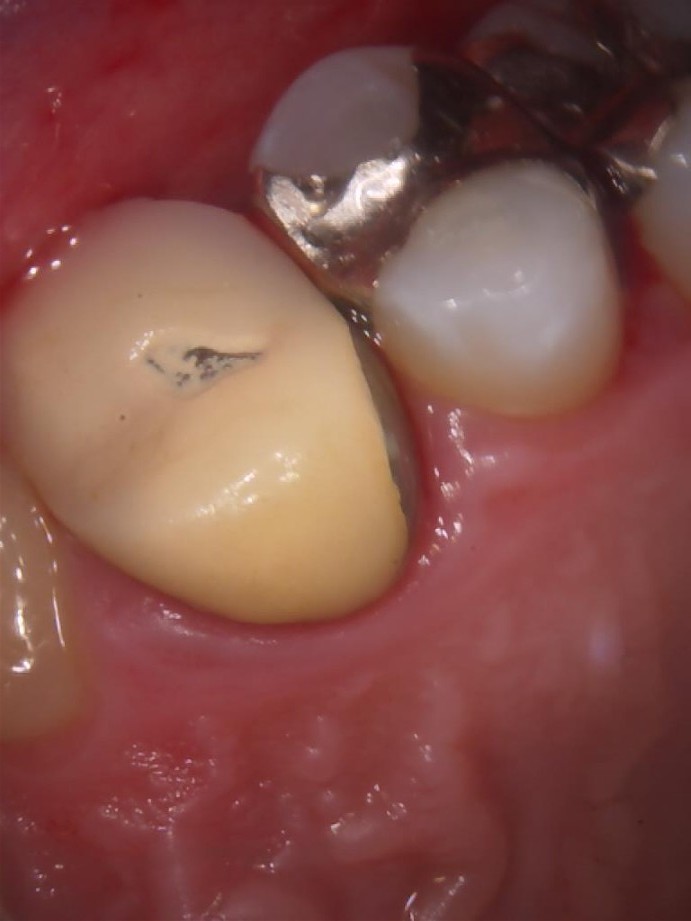

被せ物が欠けたときにはご相談を!

こんにちは! もとす・ファミリー歯科院長の若松諒です。 今回は被せ物が欠けた場合の対応についての投稿になります。 歯医者で被…